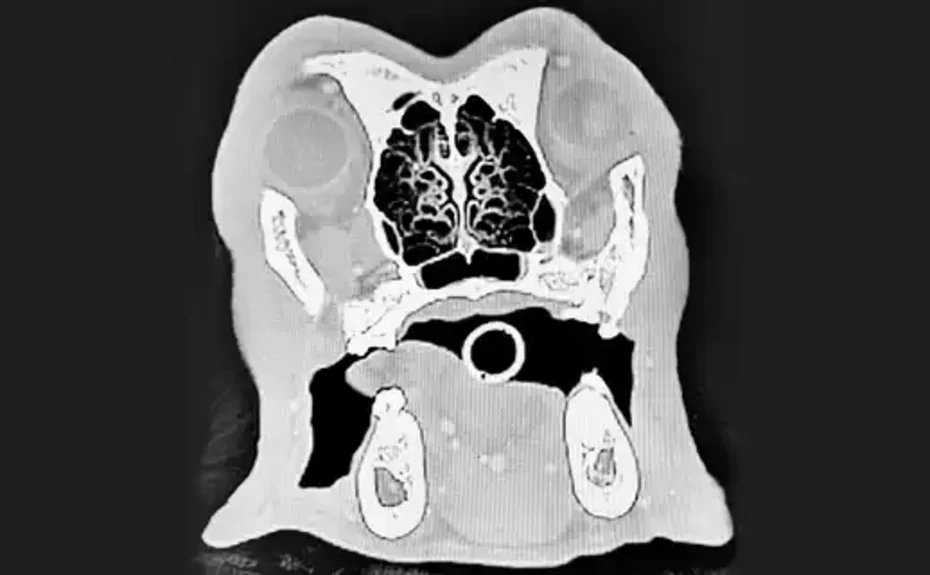

HNO / Oromaxillofaziale - Chirurgie

Unser Spektrum der HNO / Oromaxillofazialen - Chirurgie umfasst:

• „Brachycephales Obstruktives Atemnot-Syndrom“ (BOAS) der kurzköpfigen Rassen (Bulldoggen, Mops, Boston Terrier, Perserkatzen, u.a.): Rhinoplastiken (Korrektur von verengten Nasenöffnung), partielle Staphylektomie (Gaumensegelplastik), Sacculektomie (Stimmtaschenresektion),

• Mittelohr, äußerer Geörgang: Myringotomie, Bullaosteotomie, TECA-Totale Ablation des Gehörganges, laterale Gehörgangsresektion, (partielle) Pinnektomie bei Tumorerkrankungen, Hautplastiken, Othämatomoperation

• Trepanation